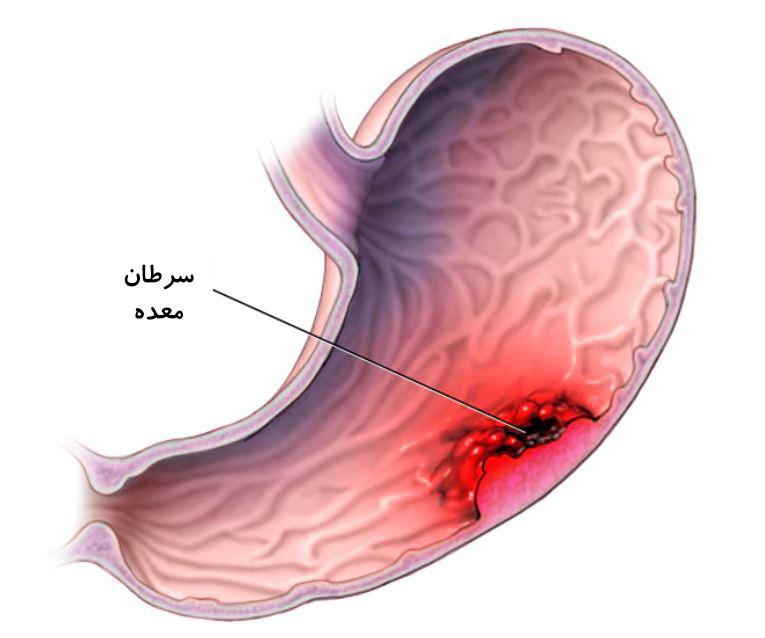

سرطان معده یکی از بیماریهای خطرناک و شایع است که میتواند بر روی سلامتی افراد تأثیرات

جدی بگذارد. این بیماری معمولاً به دلیل تشکیل تودههای خبیث در بافت معده رخ میدهد. اما علل ابتلا به سرطان معده متنوع هستند و در این مقاله به بررسی برخی از این علل میپردازیم.